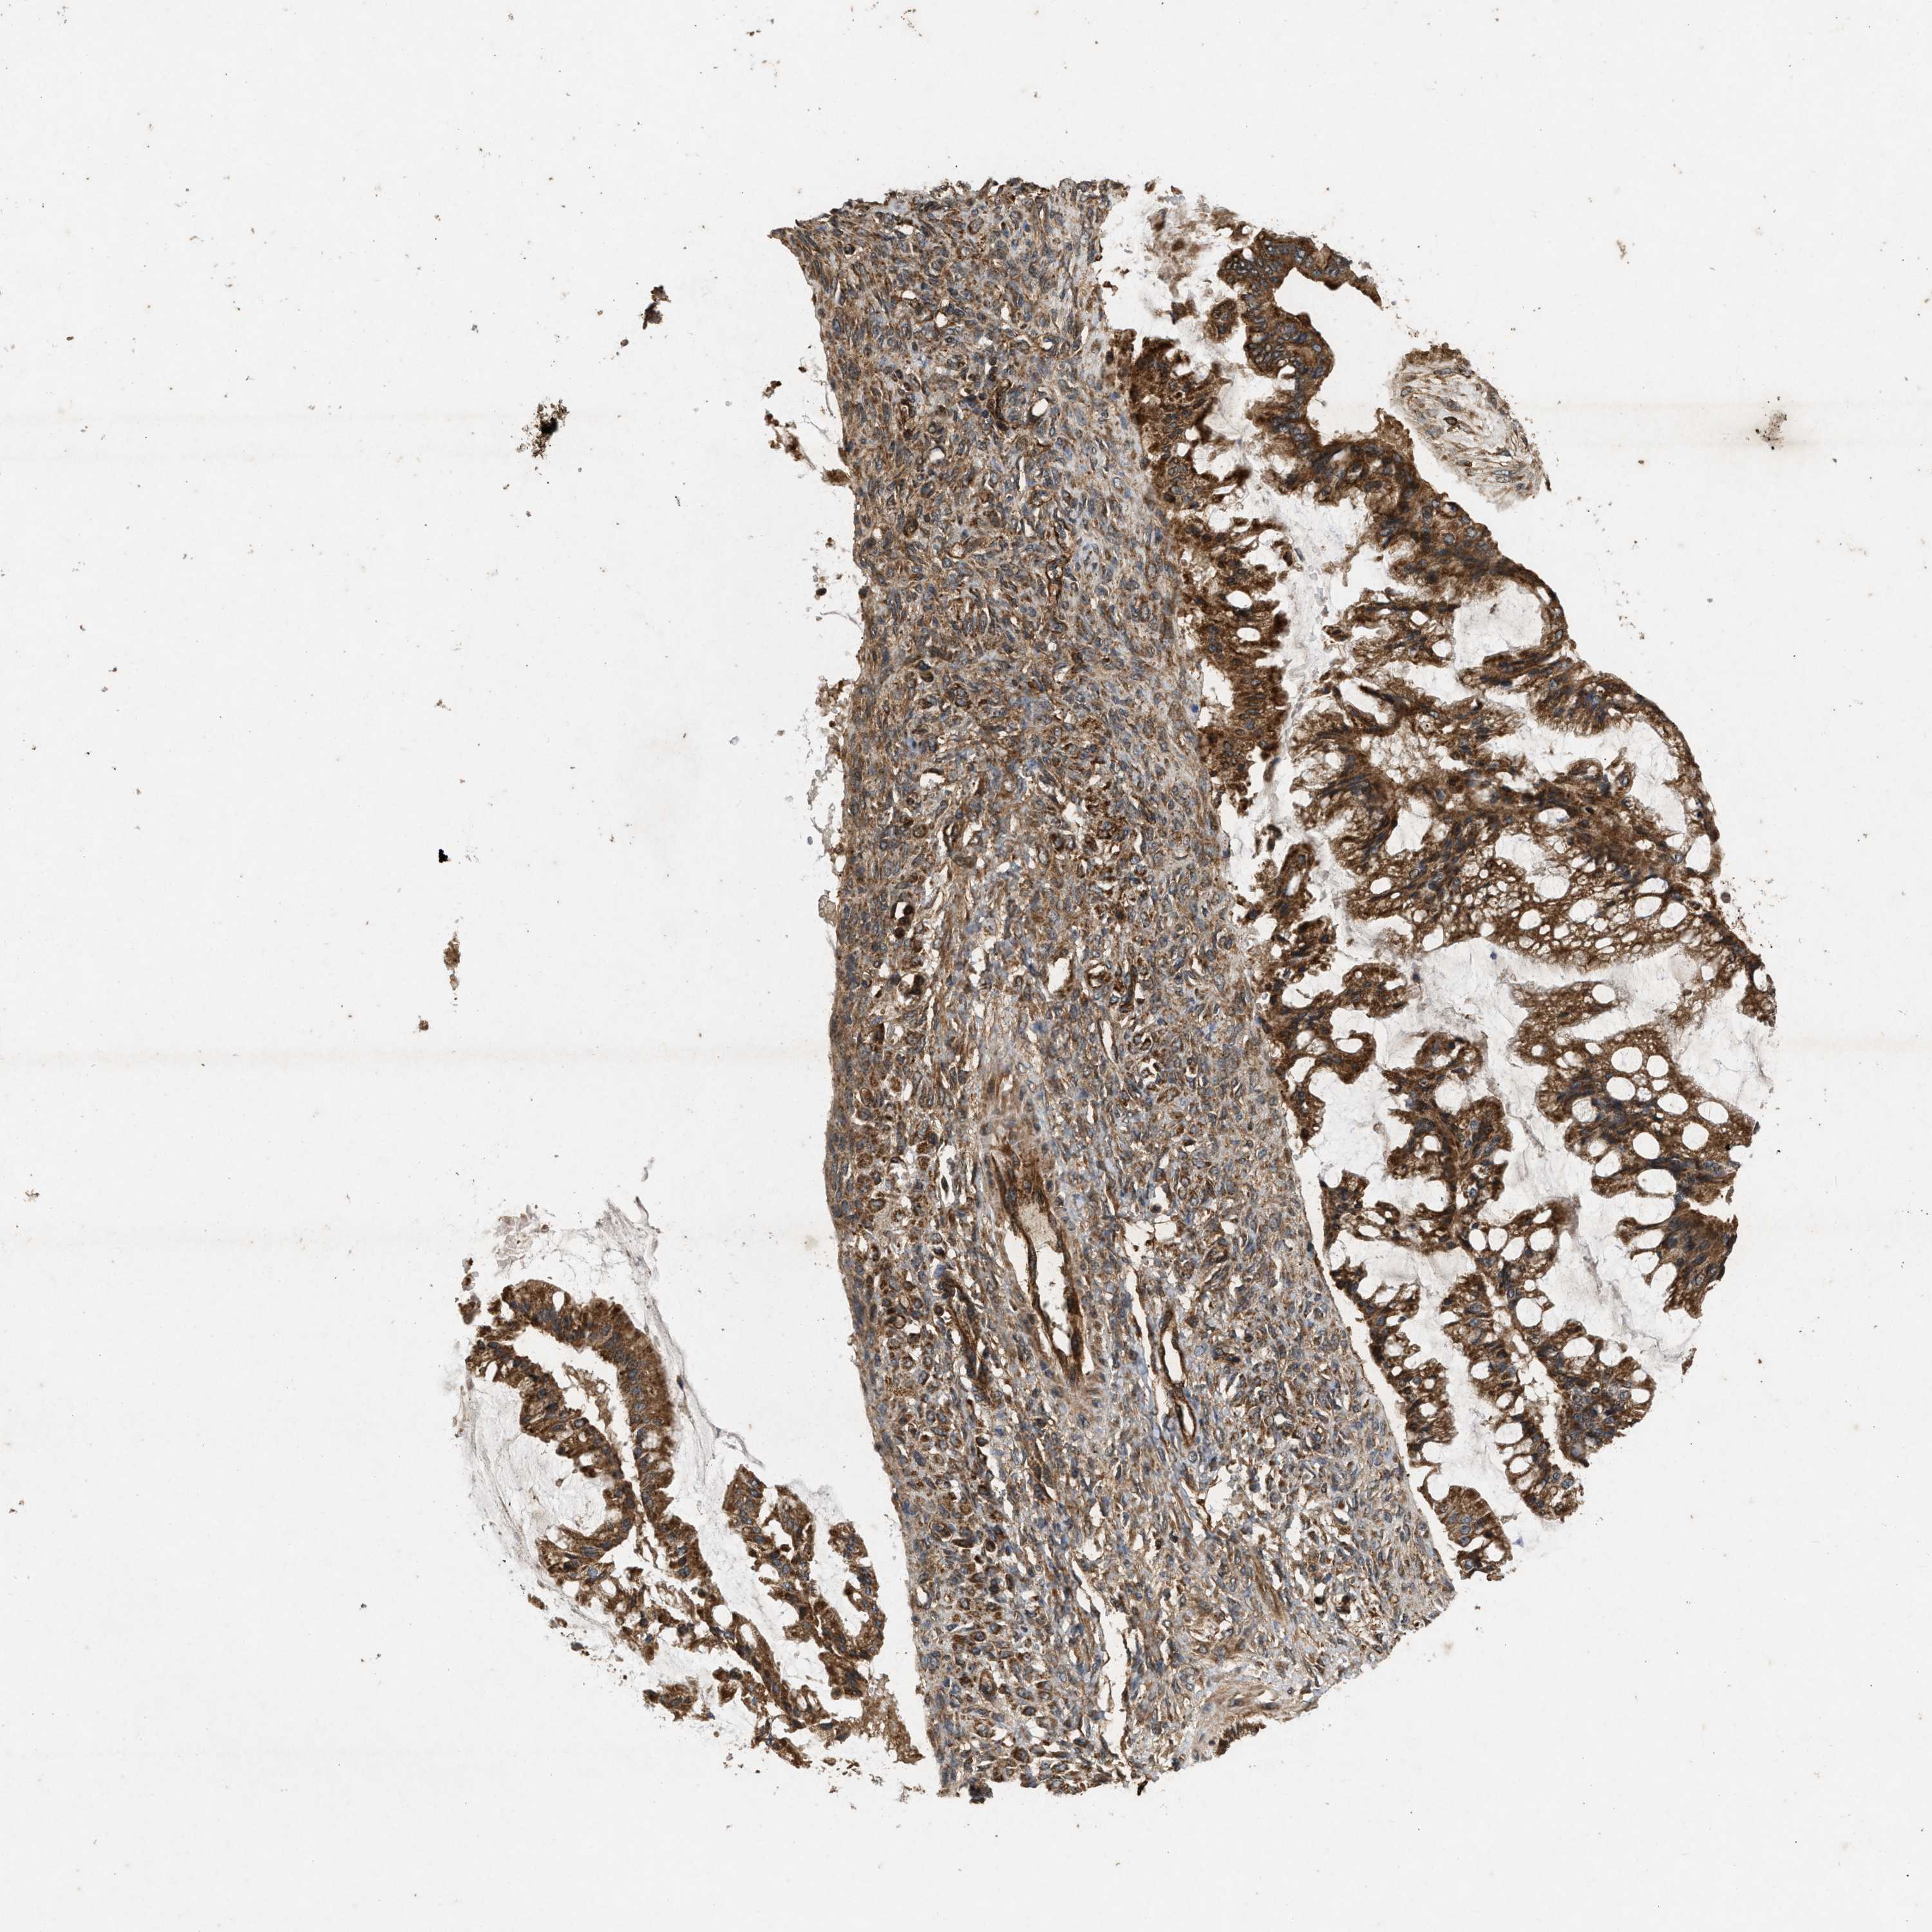

OVARIAN CANCER - Protein expressioni

A mouse-over function shows sample information and annotation data. Click on an image to view it in a full screen mode. Samples can be filtered based on level of antibody staining by selecting one or several of the following categories: high, medium, low and not detected. The assay and annotation is described here.

Note that samples used for immunohistochemistry by the Human Protein Atlas do not correspond to samples in the TCGA dataset.

Antibody stainingi

Antibody staining in the annotated cell types in the current human tissue is reported as not detected, low, medium, or high, based on conventional immunohistochemistry profiling in selected tissues. This score is based on the combination of the staining intensity and fraction of stained cells.

Each image is clickable and will lead to virtual microscopy that enables deeper exploration of all samples and also displays staining intensity scores, fraction scores and subcellular localization as well as patient and tissue information for each sample.

Antibody CAB018383

Cystadenocarcinoma, serous, NOS